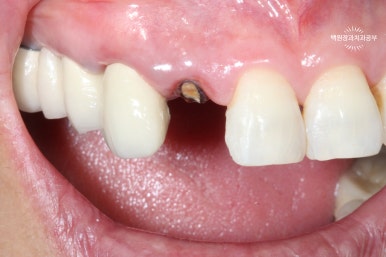

오른쪽 위 가쪽 앞니 (측절치)가 뿌리만 남아있는 것을 보실 수 있을겁니다. (잔존 치근)

대부분.. 아니 거의 100이면 100 일반 치과에서 발치 즉시 임플란트를 권하게 됩니다.

뿌리만 남은 치아 살리는 방법입니다. ㅎㅎ 임플란트를 하지 않을 수 있어요!!!

그치만 이러한 경우가 외과적 정출술의 가장 좋은 예 입니다.

키워드는 '건전한 치아 뿌리'와 '뿌리가 하나인 치아'